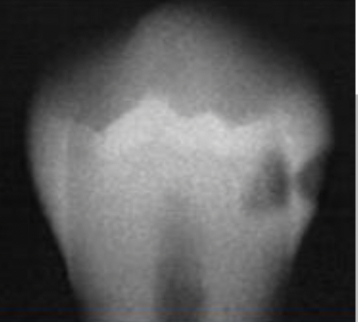

What is going on in the following radiograph?

Moderate Occlusal Caries